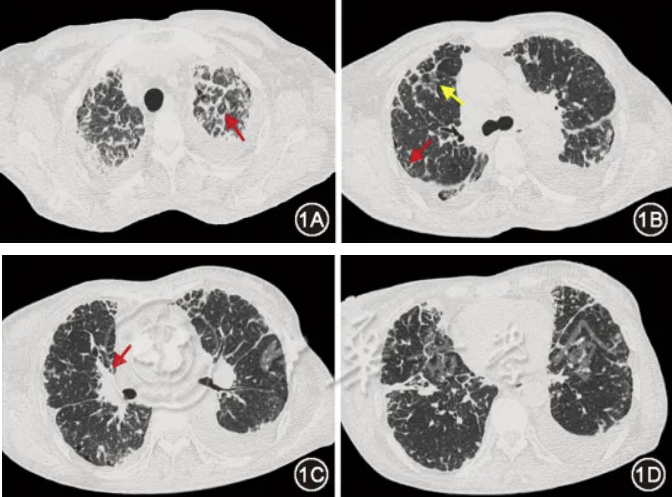

图2 治疗前(2024年9月10日)胸部CT:双侧胸腔积液(图2A箭头)、胸膜增厚(图2B红箭头),纵隔多发肿大淋巴结(图2B黄箭头)

患者女,66岁,因“活动后气短、下肢水肿1年,加重1个月余”于2024年11月25日入院。2023年12月起患者出现活动后气短、下肢水肿,逐渐加重,日常卧床。多次于外院就诊,CT示支气管血管束增粗、小叶间隔增厚、网格及磨玻璃影,伴纵隔淋巴结肿大、胸膜增厚及胸腔积液;纵隔淋巴结活检病理:多量吞噬炭末的异物巨细胞;外院考虑“间质性肺炎伴感染”,间断予抗感染治疗无效。2024年6月14日患者就诊于我院门诊,查血管紧张素转化酶(ACE)77 U/L(参考范围:12~68 U/L),拟诊为结节病,予口服泼尼松40 mg、1次/d,共2周,此后每周减2.5 mg;吗替麦考酚酯0.5 g、2次/d。患者气短仍加重,并新发右乳肿大。2024年9月于我院住院,气管镜下见多发支气管黏膜充血、散在炭末沉积;再次行纵隔淋巴结活检,病理可见少许巨核细胞;支气管肺泡灌洗液(BALF)细胞分类:巨噬细胞百分比99%,中性粒细胞百分比0.5%,淋巴细胞百分比0.5%;BALF T细胞亚群:CD4+/CD8+T细胞比值0.8。完善胸腔积液检查:黄色浑浊,白细胞总数147×106/L,单核细胞百分比93.2%,乳酸脱氢酶150 U/L,腺苷酸脱氨酶10.6 U/L,甘油三酯0.1 mmol/L。胸腔积液及血结核感染T细胞检测(T-SPOT.TB)阳性。胸腔积液、BALF细胞学检查未见瘤细胞。乳腺超声及钼靶:右乳水肿改变;CT表现同前(图1,图2)。结合上述检查,考虑结节病诊断不成立,于2024年9月末停用泼尼松及吗替麦考酚酯。由于病因未明,不除外结核感染,予异烟肼、利福平、乙胺丁醇诊断性抗结核,引流胸腔积液后出院。出院后1个月,患者气短、右乳肿大、胸腔积液仍加重,自行停用抗结核药物,于2024年11月25日再次入院。患者有双侧腕管综合征病史3年,否认疫区及牧区旅居史、家族肿瘤病史。